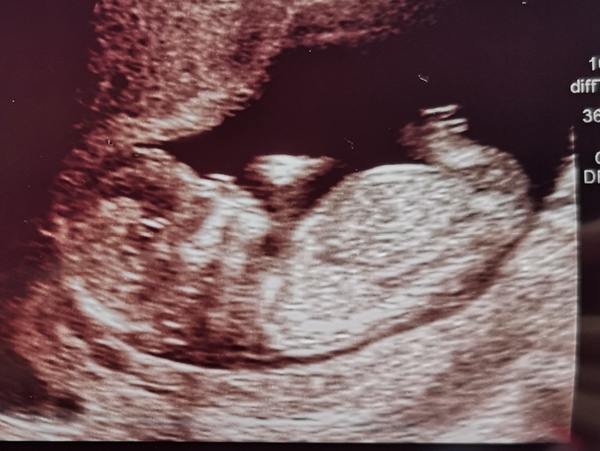

Had my scan. They bumped me a day ahead! Now 13+4 which is great, everything is on track. He or she looks so much bigger. I can't believe it! Especially now I've just looked back on my 10wk scan. He has done now and toes. I wish i could see him again, i can't get enough of seeing him move about.

He didn't want to let them do measurements either. Was determined to not turn. Stubborn!

And i could see his nose and mouth... Naaawww.

I've been lurking about for a while until my 12 week scan. Anyway I finally got to see a healthy baby this afternoon so decided to finally say hello.

We had a very wiggly baby, arms and legs were everywhere, but we got some lovely pictures.

Scan went well this morning, little one didn't get to come in so husband had to stay outside with her. All was good though and my due date has changed from the 20th to the 17th which makes me 13 weeks today!

Congrats that's a lovely scan pic!